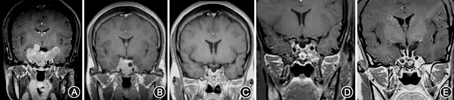

治疗后软组织肿胀等症状明显好转,1周后GH 6.54 μg/L、IGF-1 498 μg/L,持续治疗4个月后复查MRI示肿瘤较治疗前缩小54.5%,行经蝶手术,术后4个月复查ICA周围少许肿瘤有残留,肿瘤体积为治疗前的7.6%,行γ刀治疗,术后1年半IGF-1降至正常,现术后6年,临床症状缓解,月经正常,持续GH和IGF-1监测均正常(图1)。

例1肿瘤呈分叶状,侵犯海绵窦、包绕双侧ICA并向两侧颞叶生长,对该例选择合适的治疗方法是非常困惑的。根椐以往经验,很多医疗单位会选择开颅、分次开颅、经蝶联合开颅、放疗等综合治疗手段,可能会给患者带来更多手术创伤,疗效也难以预测。术前予Lanreotide 40 mg/2周治疗,治疗4个月后复查MRI发现肿瘤明显缩小,两颞叶方向生长的肿瘤明显向中线和鞍内方向回缩,为经蝶手术尽可能多切除肿瘤创造有利条件。患者第1次经蝶手术后,残余肿瘤体积为药物治疗前的7.6%,术后行伽马刀治疗,术后已随访6年,临床症状缓解,GH和IGF-1正常。对于手术前药物治疗能否提高手术疗效仍需更多数据支持。研究显示,术前SSA治疗虽能降低GH和IGF-1水平,缩小肿瘤体积,而对手术治愈率无影响[2,3,4],另有研究则显示,术前SSA治疗可提高手术治愈率[5]。以下情况可选择药物作为一线治疗:对于预期手术无法完全切除的大腺瘤且无肿瘤压迫症状者,不愿意接受手术以及不适合接受手术者,如明显呼吸功能障碍、心功能不全和严重代谢紊乱(包括心肌病、重度高血压和未能控制的糖尿病等),因气道问题麻醉风险较高者,术前药物治疗可以改善心肺功能以降低麻醉和手术风险[6]。